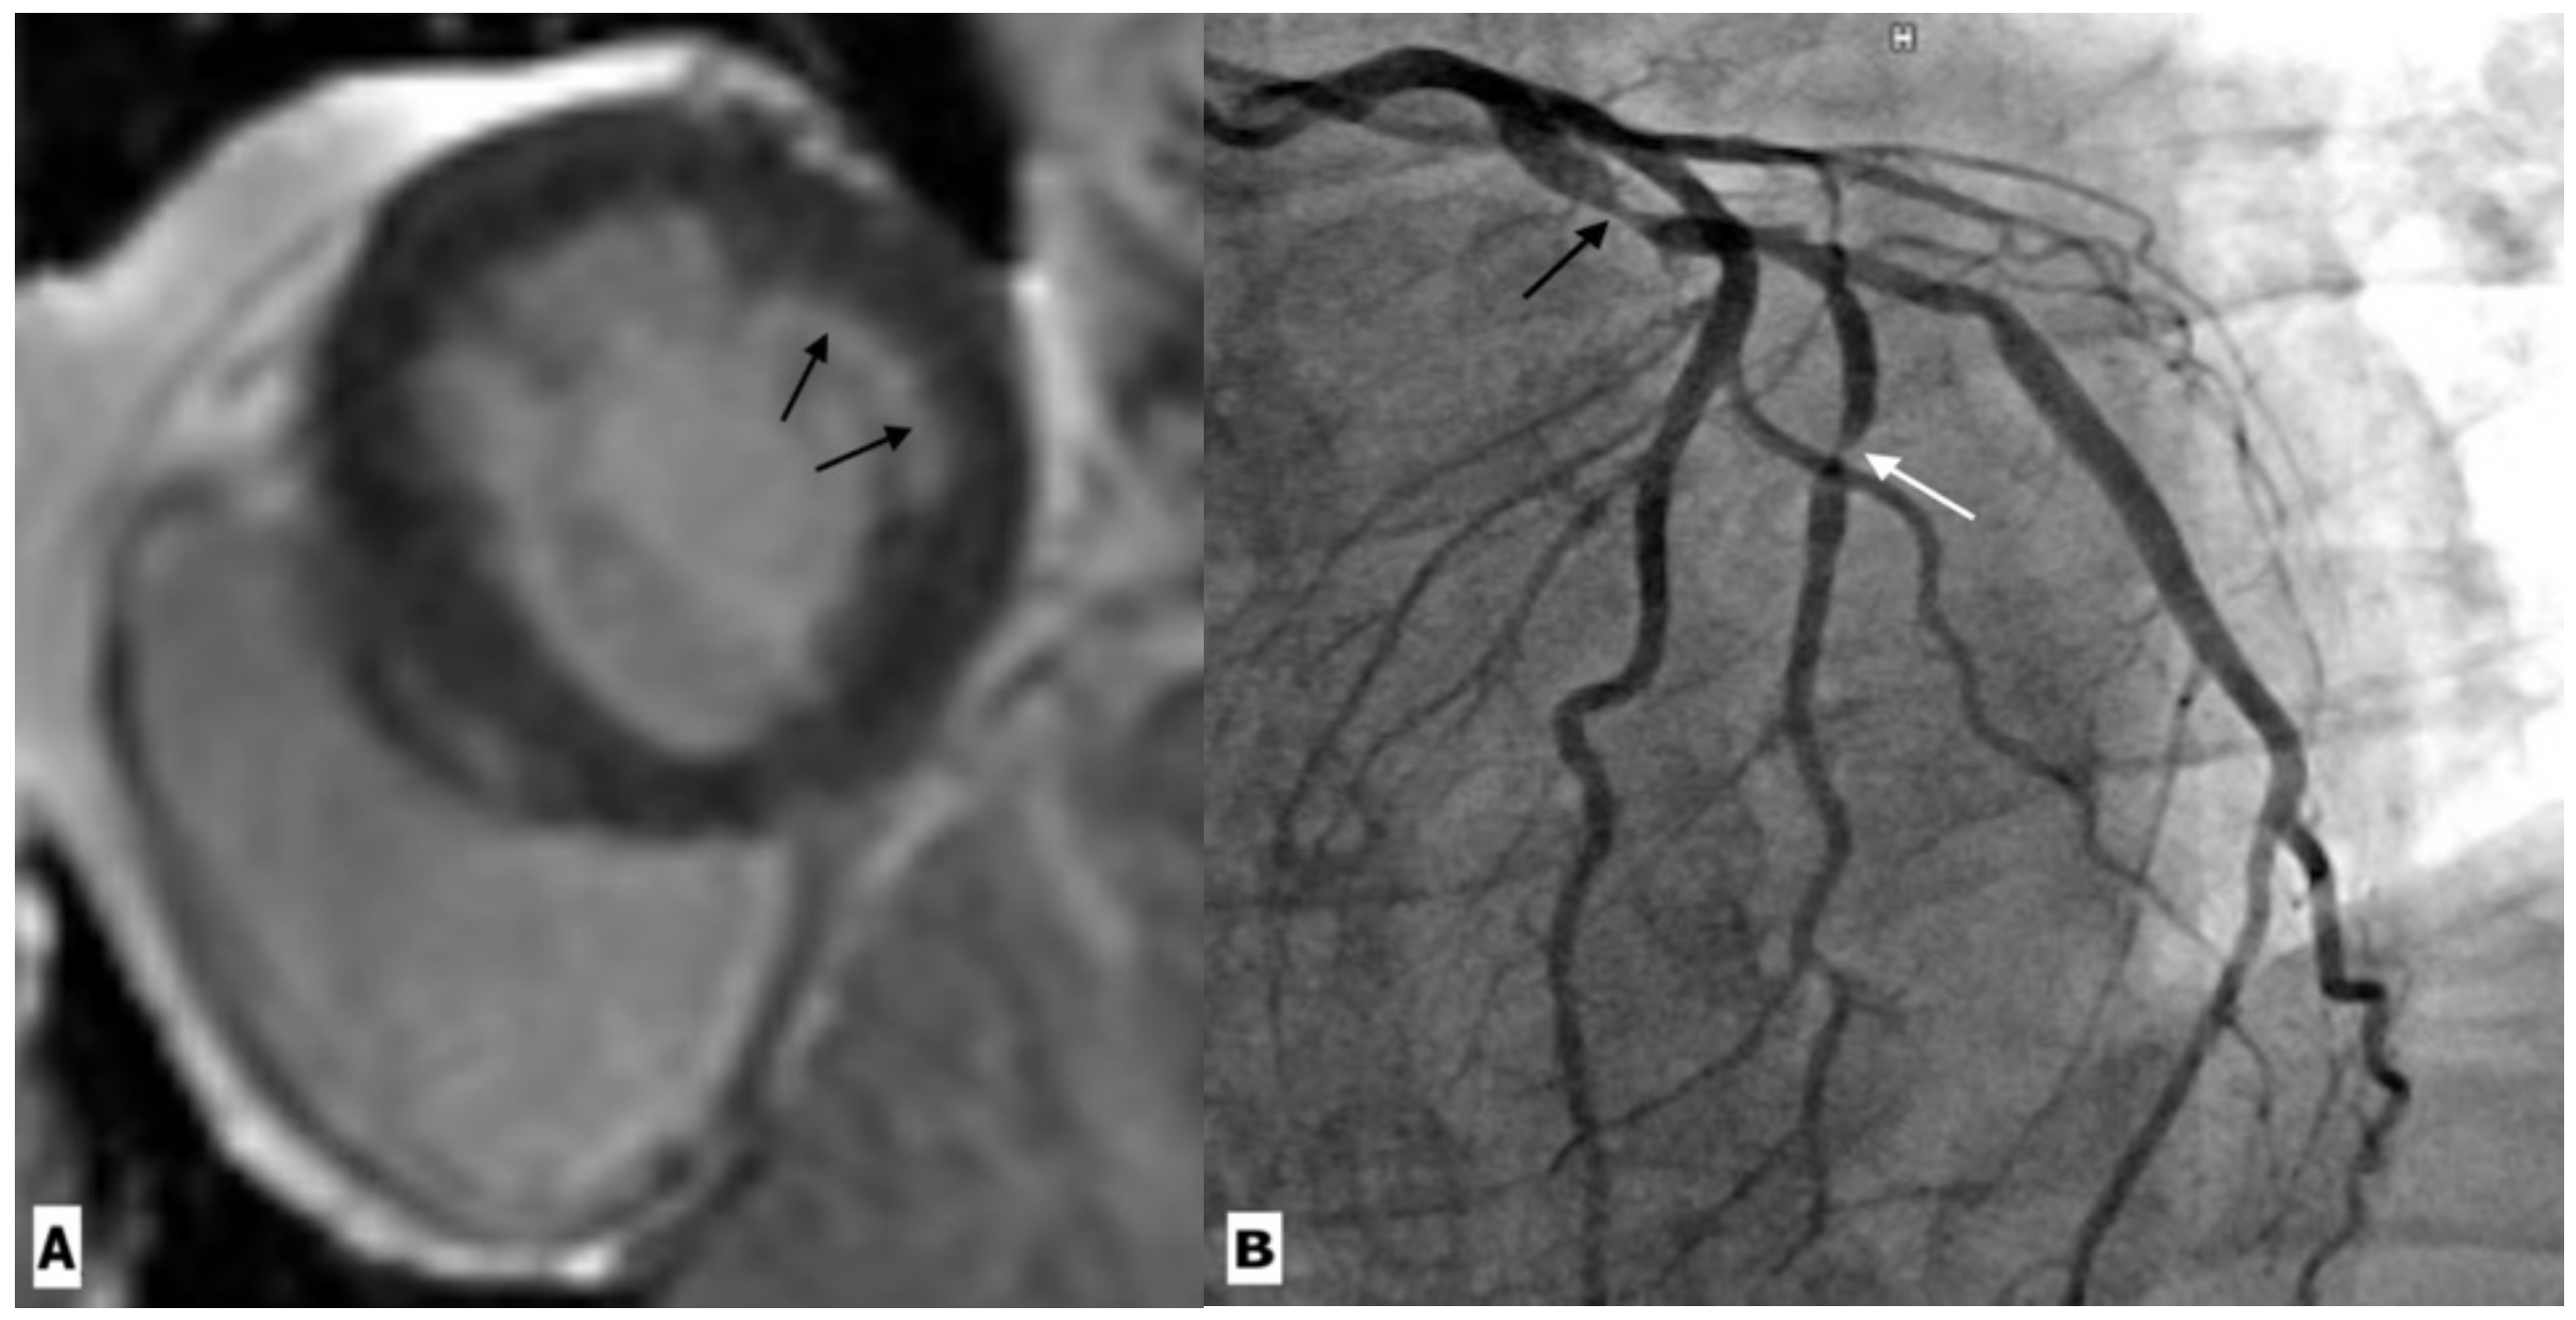

| Coronary artery disease | Raggi, P. et al. | Prospective observational study | 843 patients | CT | In a median follow-up of 2.8 years, it was seen that a CAC score of 100 was associated with 3.3-times higher odds of myocardial infarction, independent of gender and age. |

| Zanni, M.V. et al. | Cross sectional study | 101 patients and 41 controls | CTA | The study showed an increased prevalence of low-attenuation coronary plaque in HIV-positive men compared to age-matched HIV-negative healthy controls. | |

| Hoffmann, U. et al. | Cohort study | 755 HIV infected patients | CTA | Atherosclerotic plaque was seen in 49% patients. Luminal obstruction of at least 50% was rare (3%), but vulnerable plaque were more frequently observed (23%). Overall, 35% of patients demonstrated coronary artery calcium score scores greater than 0. IL-6. LpPLA2, oxLDL, and MCP-1 levels were higher in those with plaque compared to those without. | |

| Irene, J. et al. | Cross sectional study | 27 HIV infected patients | MR angiography | More than half of the subjects showed CAD with luminal narrowing detected on MR angiography. There was no association between CAD and previous cardiac conditions (viral pericarditis and zidovudine related cardiomyopathy). | |